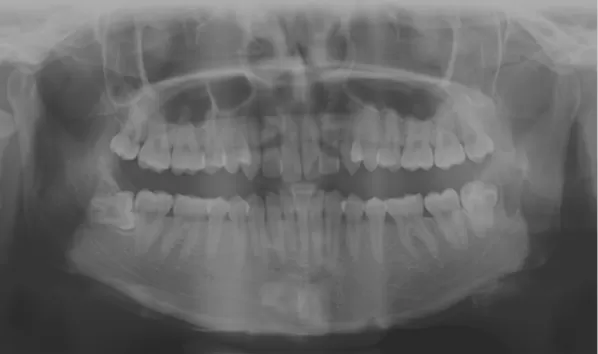

X-rays before treatment

[Panoramic Radiography/Lateral Cephalogram]